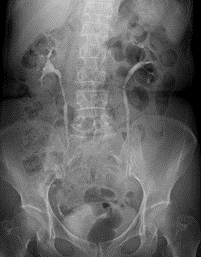

腎盂造影(IVP:IntraVenous Pyelography)

腎盂・腎杯・尿管・膀胱・尿道までの全尿路像が得られます。造影剤注入前に単純写真を撮影します。

その後造影剤を静脈より注入し、5分、10分、15分、(必要に応じて30分)と時間を追って撮影をします。

腎盂造影